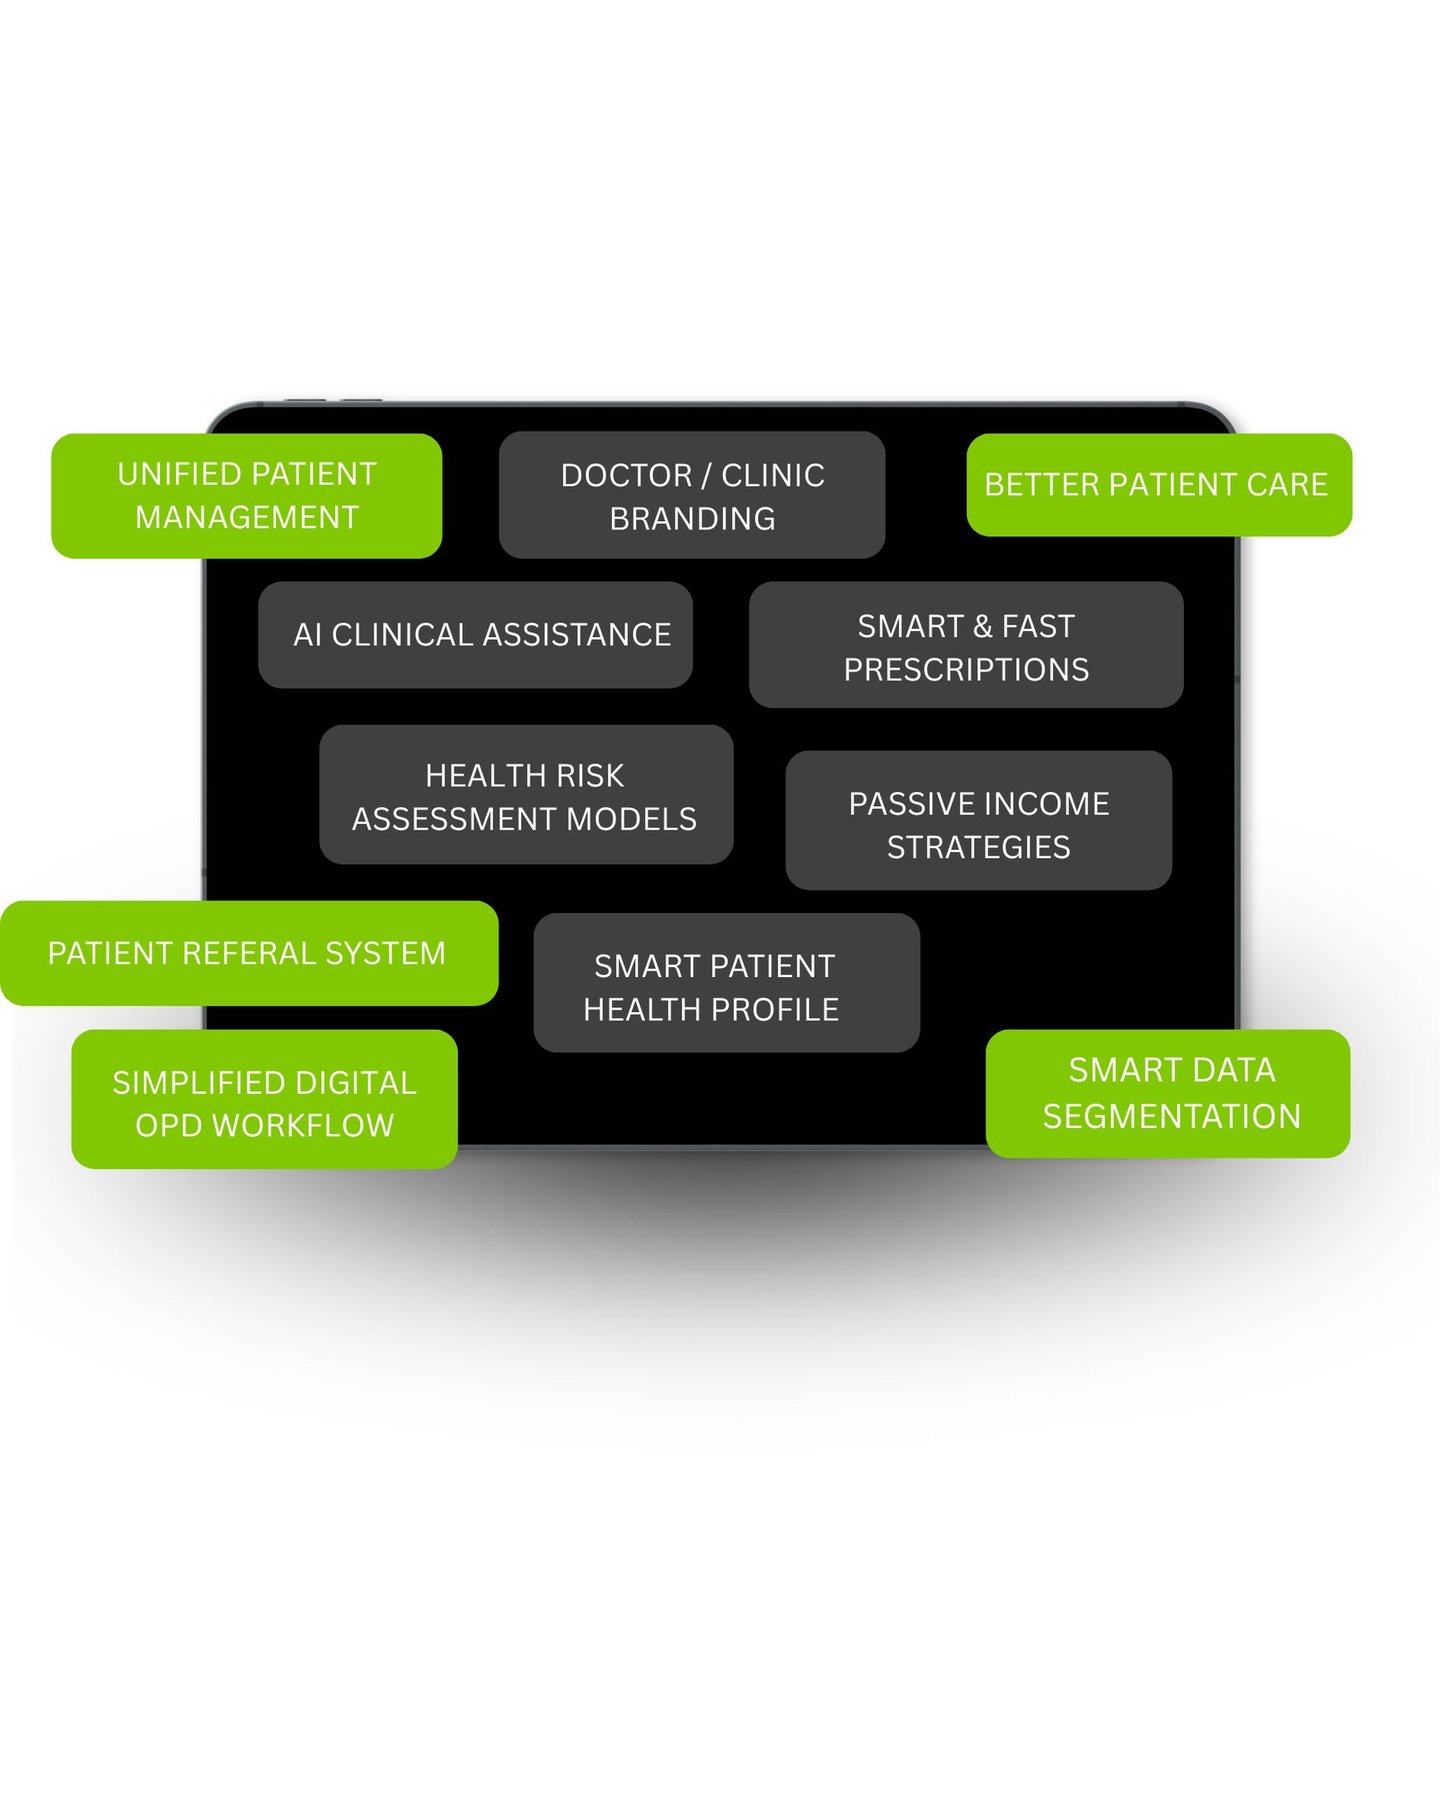

PHIA.CARE helps doctors run smarter Clinics / Polyclinics with AI-assisted prescriptions, instant risk reports, and fully digital patient management—so you focus on treatment, not paperwork.

We empower Doctors, clinics and hospitals with our technology-enabled platform, enabling efficient and structured patient management through single account and health risk evaluations at the OPD level.

THE SOLUTION

PHIA.CARE is your digital clinic assistant.

It simplifies everything—from patient entry to follow-up

Saves time.

Better follow-up.

Profesional websites and branding

Better patient experience through personal health profiles for them.

Easy OPD workflows in few taps.

Increased revenue.

AI assisted health summaries & prescription writing